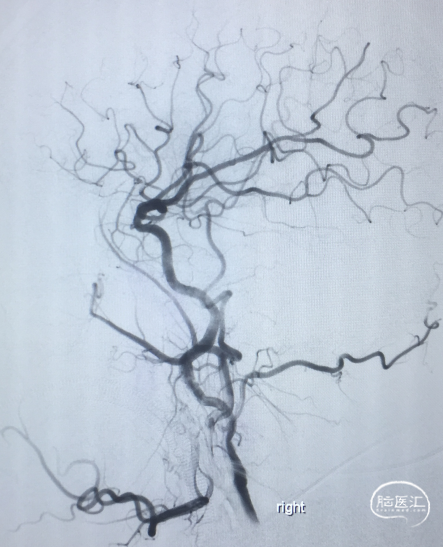

术前DSA:LICA正侧位及工作角度造影显示前交通动脉瘤

术前DSA:RCCA正侧位造影